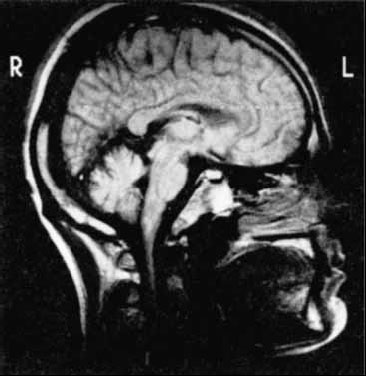

Рис. 2.17. Снимки мозга, полученные с помощью метода ядерно-магнитного резонанса (Carlson, 1992).

Поскольку водород содержится не в одинаковых концентрациях в разных тканях, что зависит как от структуры ткани, так и от ее метаболической активности, то при сканировании излучения этот факт используется для создания визуальной картины тканей. Получаемые с помощью указанного метода картины яснее и четче, чем изображения, представленные методом компьютерной томографии. Однако использование этого метода является более дорогим по сравнению с другими (рис. 2.17).

Метод ядерно-магнитного резонанса (ЯМР) позволяет визуализировать строение мозга, как и при компьютерной томографии, но он не связан с использованием радиоактивных лучей. Вокруг головы испытуемого создается очень сильное магнитное поле, которое воздействует на ядра атомов водорода, имеющих внутреннее вращение. В обычных условиях оси вращения каждого ядра имеют случайное направление. В магнитном поле они меняют ориентацию в соответствии с силовыми линиями этого поля. Выключение поля ведет к тому, что атомы утрачивают единое направление осей вращения и вследствие этого начинают излучать энергию. Эту энергию фиксирует датчик, а информация передается на компьютер.

Повторение циклов воздействия магнитного поля и его выключения дает достаточное количество данных для того, чтобы на компьютере было создано послойное изображение мозга. Для повышения разрешающей способности таких томографов иногда также используются контрастные вещества, содержащие таллий и гадолиний (Black e. a., 1989).

ЯМР-томограф высокого разрешения позволяет видеть клеточные структуры коры головного мозга при жизни человека (Press e. a., 1989). Наложение ПЭТ-томограмм на ЯМР-изображения дает возможность более тонко дифференцировать те или иные отделы коры и подкорковых структур (Лалянц, Милованова, 1991).